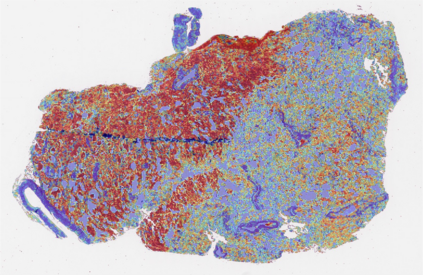

Multiple instance learning (MIL) is a powerful approach to classify whole slide images (WSIs) for diagnostic pathology. A fundamental challenge of MIL on WSI classification is to discover the \textit{critical instances} that trigger the bag label. However, previous methods are primarily designed under the independent and identical distribution hypothesis (\textit{i.i.d}), ignoring either the correlations between instances or heterogeneity of tumours. In this paper, we propose a novel multiplex-detection-based multiple instance learning (MDMIL) to tackle the issues above. Specifically, MDMIL is constructed by the internal query generation module (IQGM) and the multiplex detection module (MDM) and assisted by the memory-based contrastive loss during training. Firstly, IQGM gives the probability of instances and generates the internal query (IQ) for the subsequent MDM by aggregating highly reliable features after the distribution analysis. Secondly, the multiplex-detection cross-attention (MDCA) and multi-head self-attention (MHSA) in MDM cooperate to generate the final representations for the WSI. In this process, the IQ and trainable variational query (VQ) successfully build up the connections between instances and significantly improve the model's robustness toward heterogeneous tumours. At last, to further enforce constraints in the feature space and stabilize the training process, we adopt a memory-based contrastive loss, which is practicable for WSI classification even with a single sample as input in each iteration. We conduct experiments on three computational pathology datasets, e.g., CAMELYON16, TCGA-NSCLC, and TCGA-RCC datasets. The superior accuracy and AUC demonstrate the superiority of our proposed MDMIL over other state-of-the-art methods.